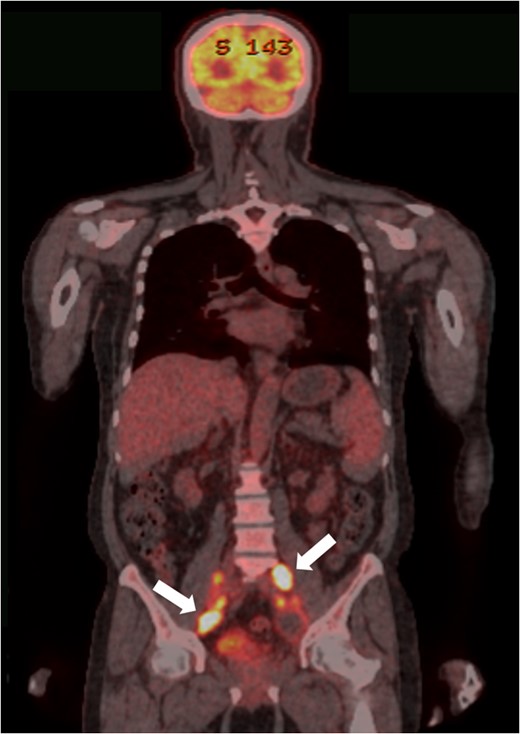

PET-CT findings. Multiple metastases to LNs along the inferior mesenteric and superior rectal arteries (arrows) are noted.

Although metastatic patterns of rectal SCC remain uncertain because of rarity, extra-pulmonary SCC originating from the gastrointestinal tract commonly metastasize to the liver, LNs and bone marrow, irrespective of the staging. Thus, the mean survival time for patients with colorectal SCC is <1 year [2]. In the present case, although liver metastasis was not observed, multiple regional LNs metastases, followed by distant LNs and bone metastases developed within the 6-month survival period.